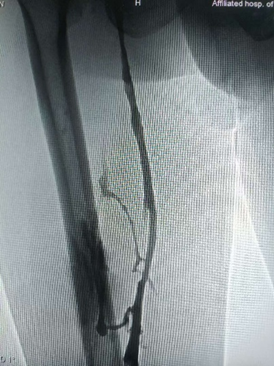

复查造影显示右下肢深静脉血流恢复通畅,拔除血管鞘,局部纱布压迫止血,包扎固定,术毕安返病房。

术后造影